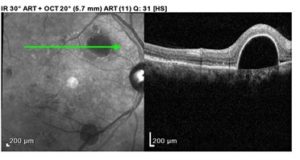

Optical coherence tomography (OCT) images were acquired OU. While center macular thickness, measuring 248 microns OD and 238 microns OS, and foveal contour were normal OU, multiple extrafoveal PEDs corresponding with the lesions noted on fundoscopy were visualized on the scans. Of note was a large PED with overlying SRF that was approximately 0.75 disc diameters in size and located superonasal to the macula OD (Figures 1 and 2). An additional PED of approximately the same size was present just inferior to the macula, and a third, smaller PED was visualized temporal to the macula OD. OS images revealed a few small PEDs in the superior, inferior and temporal macula, none of which were associated with SRF (Figure 3). All PED findings on OCT were consistent with serous PED, which typically appears dome-shaped and well-delineated with an elevated, hyper-reflective RPE overlying a hyporeflective and optically empty space.2,8,9

![]() Figure 3. Gray-scale photo of the left posterior pole. Fewer pigment epithelial detachment lesions are evident in this image. They also appear more faint compared with the pigment epithelial detachments in Figure 2. Click to enlarge |